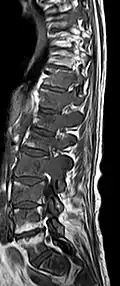

Avec l'IRM, on peut en particulier obtenir de bonnes images des tissus mous. C'est un processus idéal pour le diagnostic des métastases spinales (métastases des vertèbres). Avec l'IRM, on peut en outre rendre visible des complications supplémentaires dans la région des métastases spinales, comme des infections ou des blessures des tendons et ligaments, des œdèmes de la moelle osseuse après une fracture récente[120],[121], ou la compression de structures nerveuses[18]p. 16. Au moyen de séquences STIR, il est possible d'évaluer l'âge d'une fracture. Pour la détection des métastases, la pondération T1 avec des produits de contraste au gadolinium, comme l'acide gadotérique est particulièrement bien adaptée. Le produit de contraste s'accumule particulièrement fort dans les métastases[18],[122].

- Comparaison scanner/IRM pour des métastases ostéolytique d'un cancer du sein dans la colonne vertébrale

Scanner sagittal reconstruit, représentation dans la fenêtre osseuse. Comme la patiente avait des métastases dans toutes les régions du corps, elle ne pouvait pas lever les bras pour l'examen, ce pourquoi les mains sont présentées.

Scanner sagittale, parties molles. Outre les métastases dans la colonne vertébrale, qui envahissent en partie le canal médullaire vers l'arrière, métastases aussi dans le sternum. Plus des métastases dans le foie.

IRM natif avec pondération T1.

IRM sagittal natif avec pondération T1. On voit clairement l’extension jusqu'aux lames vertébrales.